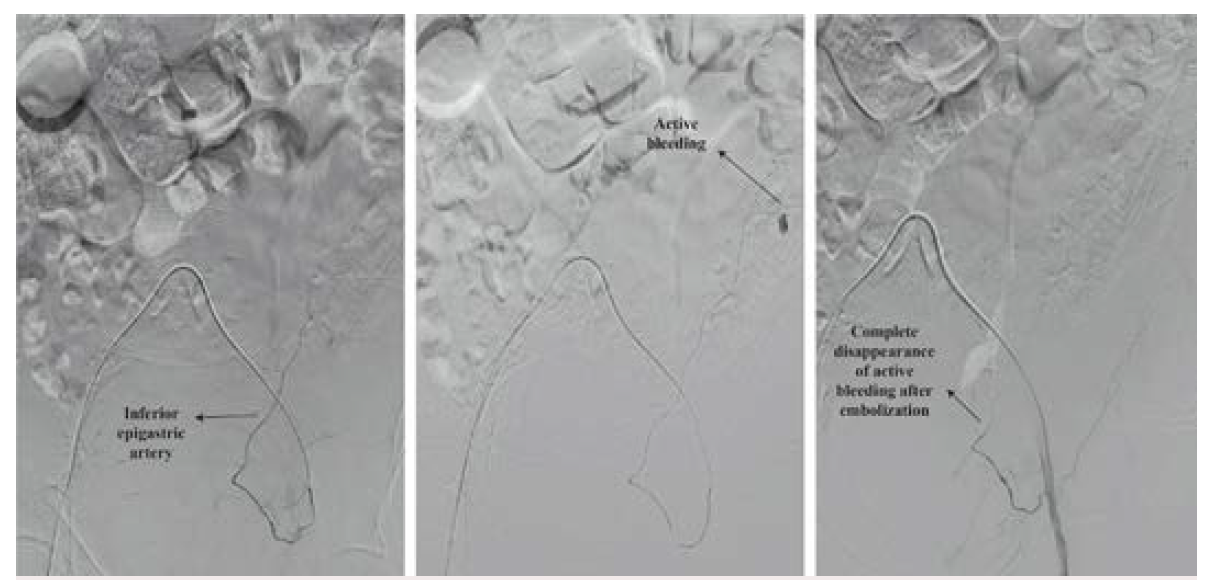

On the other hand, intravenous fluid resuscitation should be started in hemodynamically unstable patients. Red blood cell (RBC) transfusion depends on the hemodynamic status and presence of comorbid conditions.6 In an acutely hemorrhaging patient, transfusions should not be delayed awaiting laboratory tests. In addition, those patients who become hemodynamically stable with fluid resuscitation are managed as stable patients (transfuse if hemoglobin is <7g/dL).10 CT angiography must be performed as soon as possible. CT can help classify RSH according to the Berná classification as well as show evidence of active blood extravasation. The Berná grading system classifies RSH into 3 types: Type I, intramuscular and unilateral hematoma without hemodynamic compromise; Type II, unilateral or bilateral hematoma with blood between muscle and transversalis fascia, with a possible decrease in hematocrit; and Type III, hematoma associated with hemodynamic instability and with blood extending to the peritoneum and prevesical space6 (Figure 2). Active extravasation on CT angiography and a hematoma volume of >1000 mL to 1300 mL have been previously identified as predictors of conservative treatment failure.6,11 Therefore, the presence of active hemorrhage on CT angiography and/or hematoma (Type III) should promptly trigger endovascular arterial embolization or surgery. Historically, surgical ligation of the bleeding epigastric vessels was the treatment for uncontrolled RSH. However, it is well known that this technique is severely limited by the difficulties in localizing and ligating the bleeding vessel within the hematoma. Open surgery or guided drainage of RSH should be avoided when possible because it can diminish the potential tamponade effect of the rectus sheath.12 In line with this, surgery must be reserved for draining infected RSH and for controlling the bleeding in those health centers without hemodynamic and interventionist units. Selective arterial embolization, on the other hand, has been accepted as an effective and safe method for treating acute bleeding in patients with RSH.13 (Figure 3). Diamantopoulos et al reported 95.2% and 95% technical and clinical success, respectively, without rebleeding after epigastric artery embolization.14 Similarly, in a study by Contrella et al, the procedure only had to be repeated in 3 of the 32 patients who underwent endovascular embolization. In addition, no patient underwent surgery for RSH.6